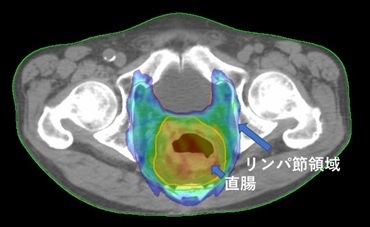

直腸がん

多くの場合、手術が標準療法です。手術での取り残しを防ぐため、手術前に薬物療法を併用した放射線治療を行うことがあります。照射線量は45Gy、照射期間は5週間です。

高齢であったり心臓や肺の機能が悪くて手術ができない場合、手術を希望されない場合は根治を目指した放射線治療を行うことがあります。照射線量は50-66Gy、照射期間は5~7週間です。

放射線治療に際し消化器内科あるいは外科の診察が必要です。

併存疾患のため手術できず薬物療法と放射線治療の併用療法で根治を目指した。

IMRTを用いて直腸がん自体には高線量を、転移しやすいリンパ節領域には予防的な線量を照射。